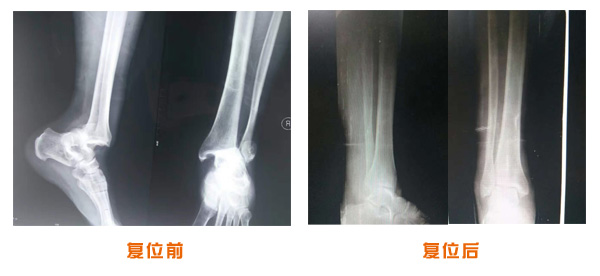

肘關節脫位骨折治療前后對比

踝關節脫位骨折治療前后對比

尺橈骨骨折治療前后

尺橈骨克雷氏骨折治療前后